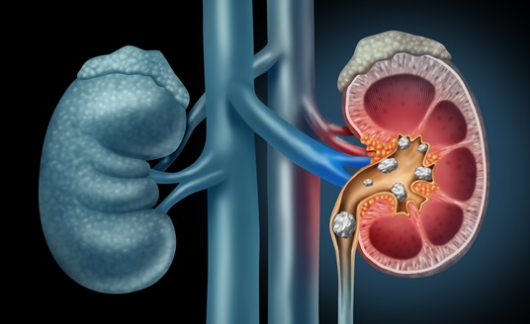

신장 결석은 신장 안에 형성된 돌을 말하며, 소변 안에 들어있는 물질들이 결정을 이루고 침착이 되어 마치 돌과 같은 형태로 콩팥 안에 생기는 질환으로 합병증을 일으 킬 수 있습니다. 시간이 지남에 따라 결석의 크기가 커지기 때문에 작은 결석이 발견되더라도 방치하지말고 정확한 검사를 통해 진단과 치료 방침을 결정해야 합니다.

신장 결석은 여러가지 물질로 구성되어 있는데, 감염이나 음식물, 약물 혹은 몸의 컨디션에 따라 소변의 칼슘이나 수산(oxalate), 요산(uric acid)의 농도가 증가하게 되면 신장 결석이 발생할 수 있습니다. 결석의 구성 성분은 이러한 생성 요인에 따라 달라집니다. 가장 흔한 신장 결석은 칼슘을 포함한 신장 결석입니다.